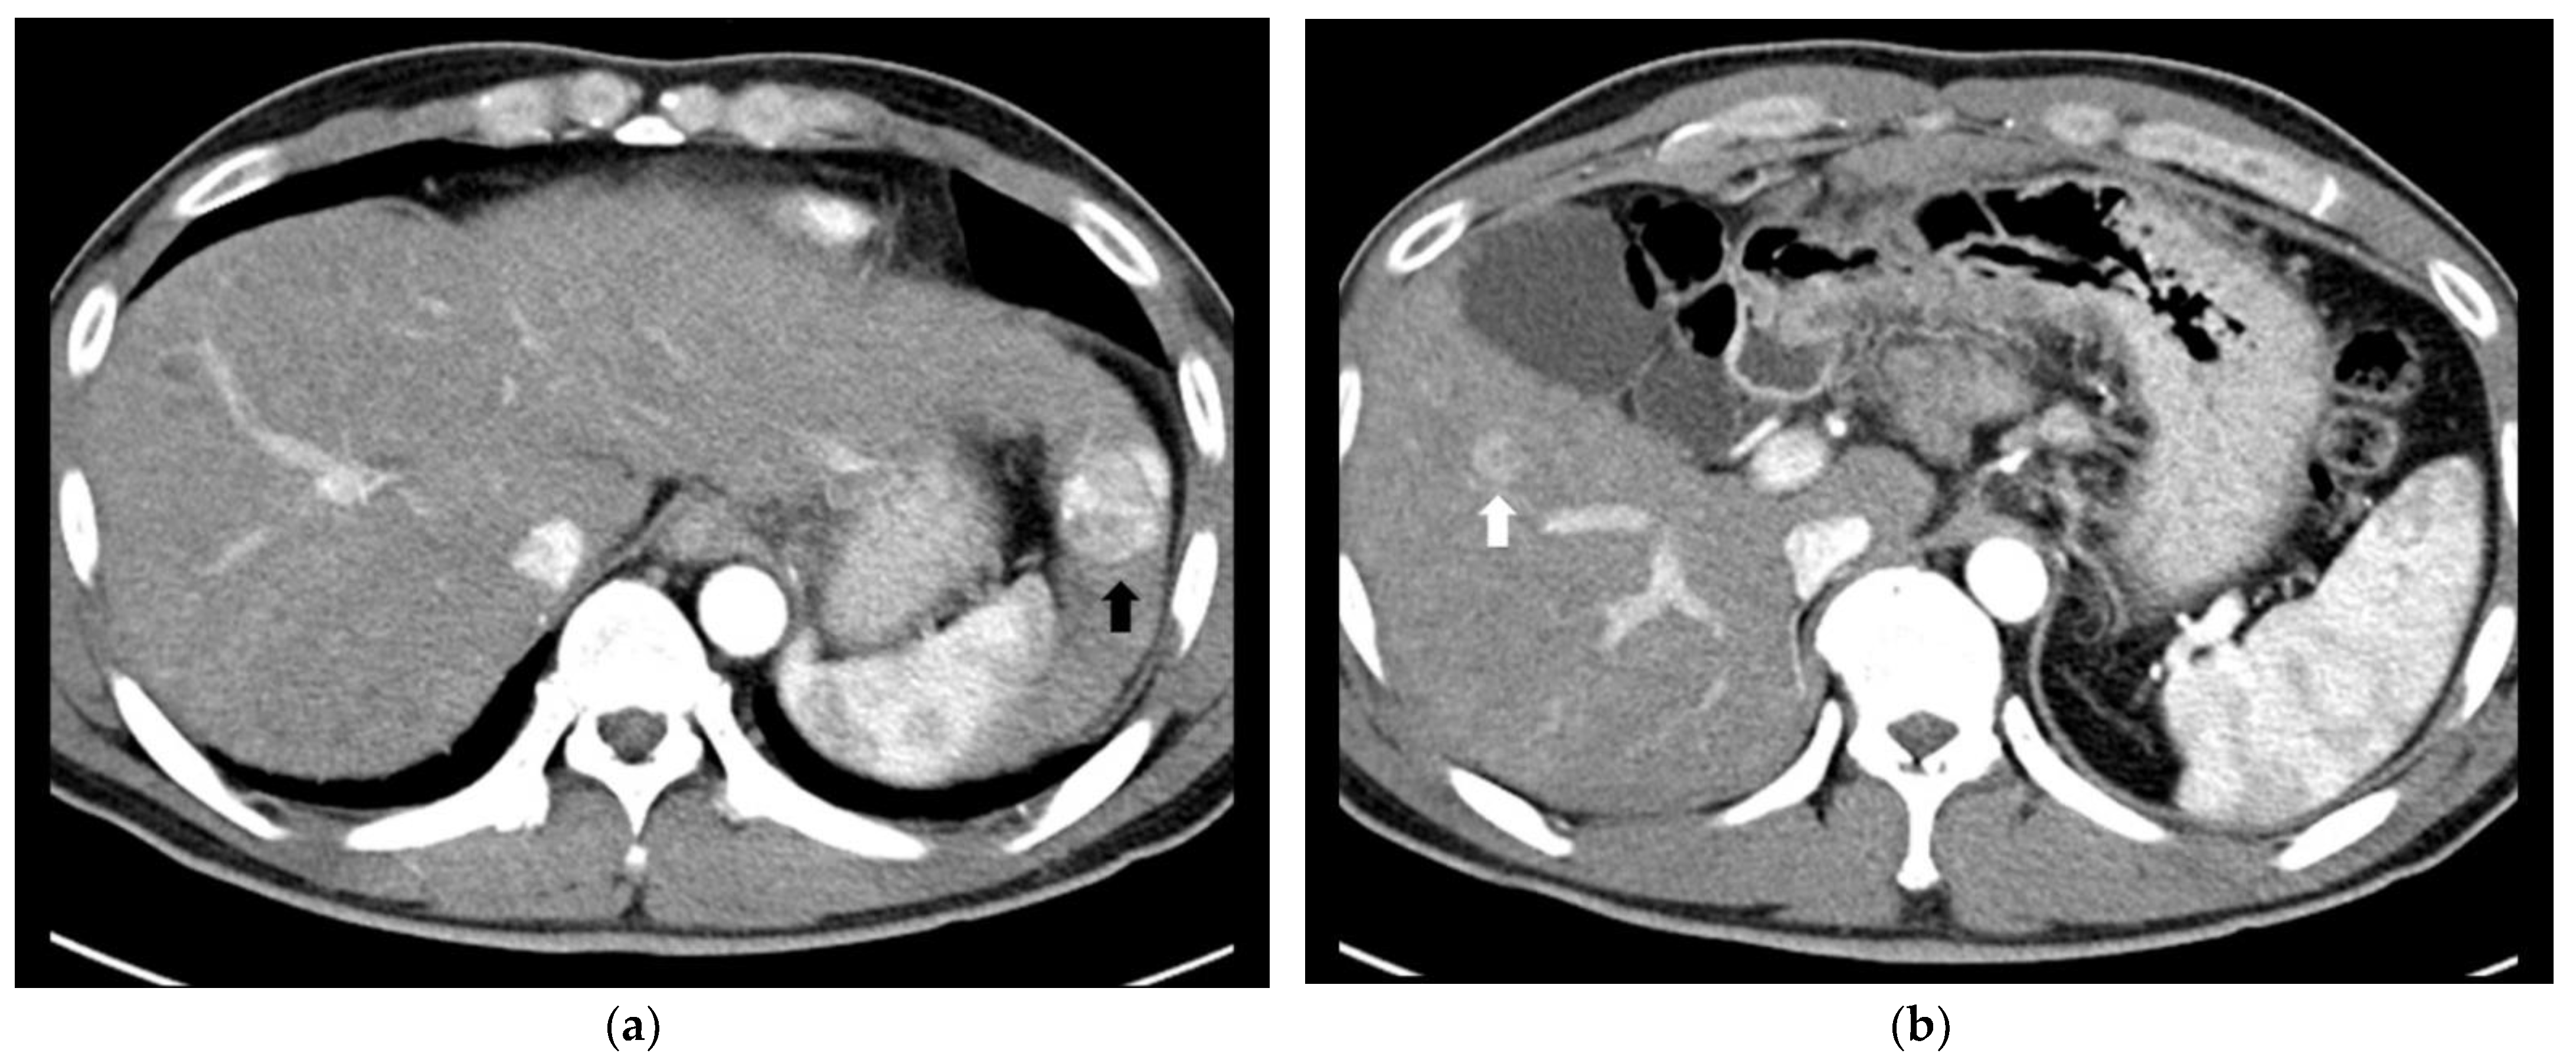

- Park, H.S.; Kim, Y.J.; Yu, M.H.; Jung, S.I.; Jeon, H.J. Real-time contrast-enhanced sonographically guided biopsy or radiofrequency ablation of focal liver lesions using perflurobutane microbubbles (sonazoid): Value of Kupffer-phase imaging. J. Ultrasound Med. 2015, 34, 411–421. [Google Scholar] [CrossRef] [PubMed] [Green Version]